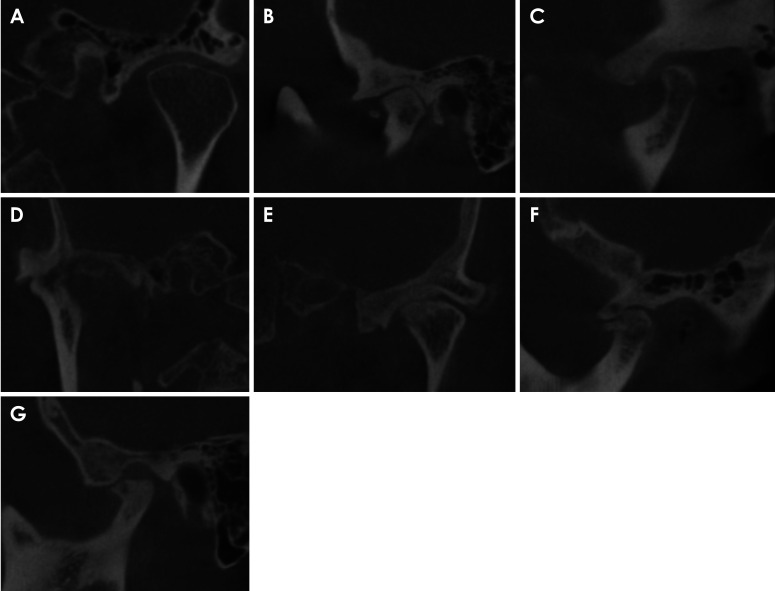

Abstract Image